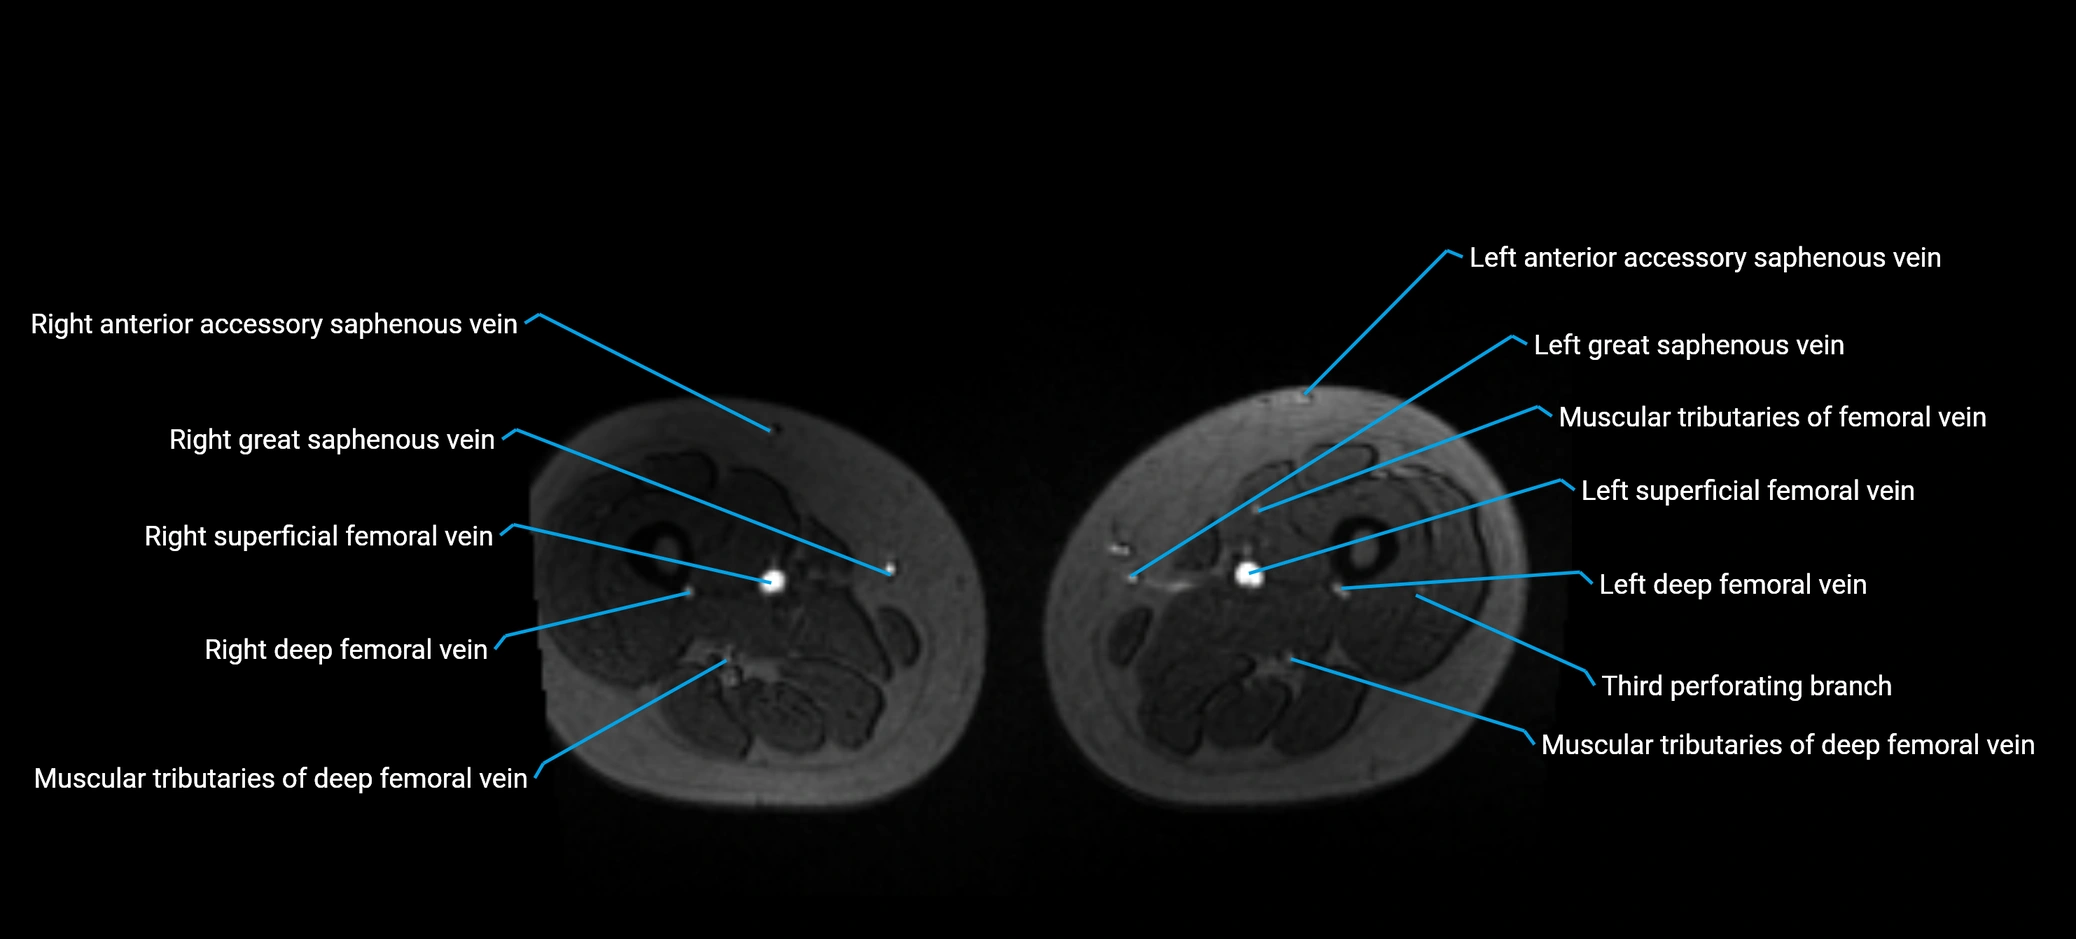

MRI image

image